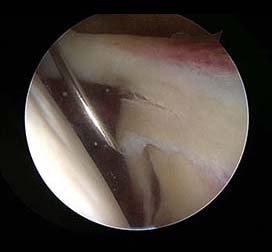

견봉쇄골 관절의 퇴행성관절염이 있어 관절경적으로 원위쇄골 골제거를 한 사진.